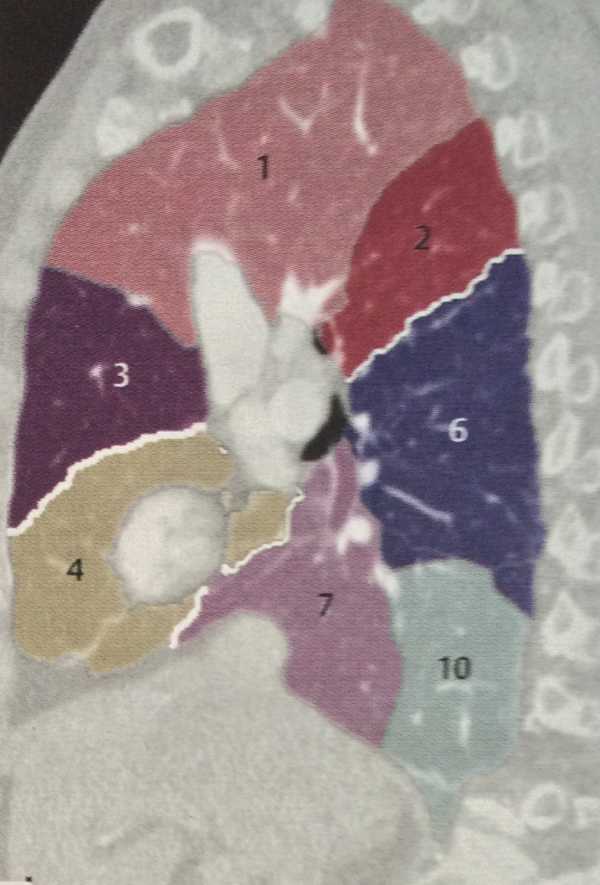

Анатомические изображения сегментов легких различных животных

Раздел: Другие животные